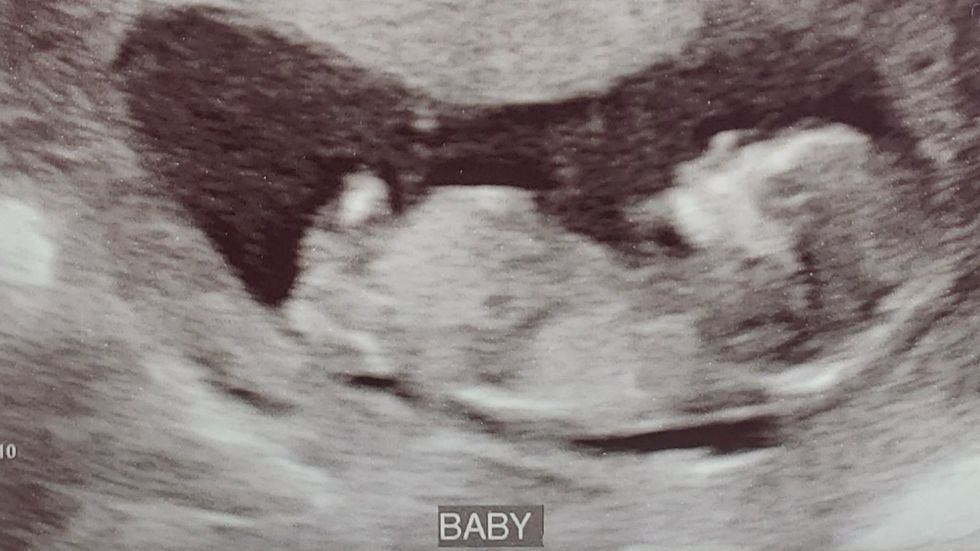

Despite the many blessings I have been given in my life in the form of a loving family, meaningful friendships, safe homes, a purposeful job that I love and the ability to share my love of music with others, the greatest blessing I have ever received is the one growing inside me. When I found out I was pregnant, the only emotions I felt were love and overwhelming gratitude. I had been chosen to be this tiny life's mom and there was nothing greater or more important than that. My fiance was just as thrilled and we immediately began making plans for a big, bright future for our little miracle, and for us.

When the COVID-19 pandemic began, our vision for this pregnancy changed. With the exception of the first one, my doctor has met me and an empty chair for every appointment. I have gone to all ultrasounds alone and only been able to share the experience with my guy through sonogram pictures and relaying messages from the techs. I am often the only one in the waiting rooms and wear a mask for the duration of my visit. The story of our labor and delivery is entirely unknown at this point but may involve having no family or friends visiting us or holding our child when he or she is born.